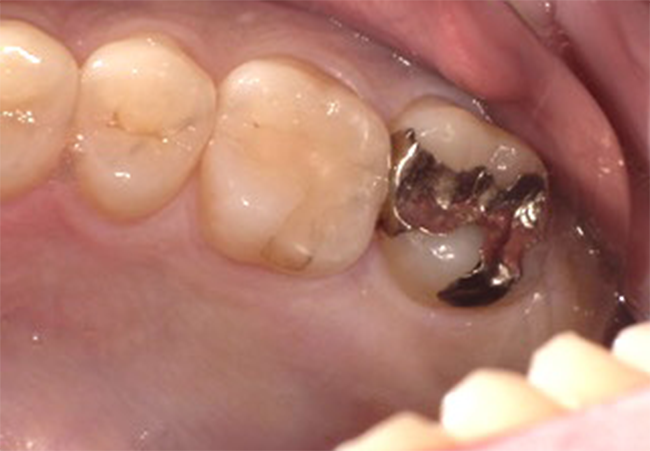

After①

年齢・性別

29歳男性

主訴

銀歯を換えたい

診査診断

審美障害

治療計画

セレックによるセラミック治療

治療期間・金額

1日2回 ¥33,000

リスク

知覚過敏、歯ぎしり等による破折